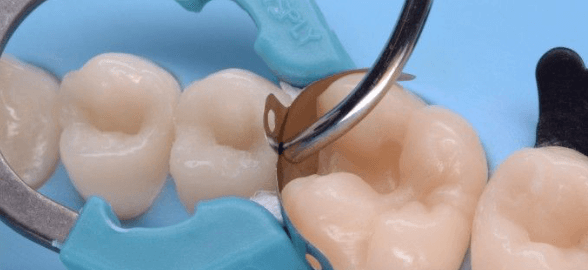

A dental matrix is a band that adapts to the surface of the tooth to be restored and reproduces the anatomical contours, replacing the missing wall or walls and containing the rest

A dental matrix is a band that adapts to the surface of the tooth to be restored and reproduces the anatomical contours, replacing the missing wall or walls and containing the rest